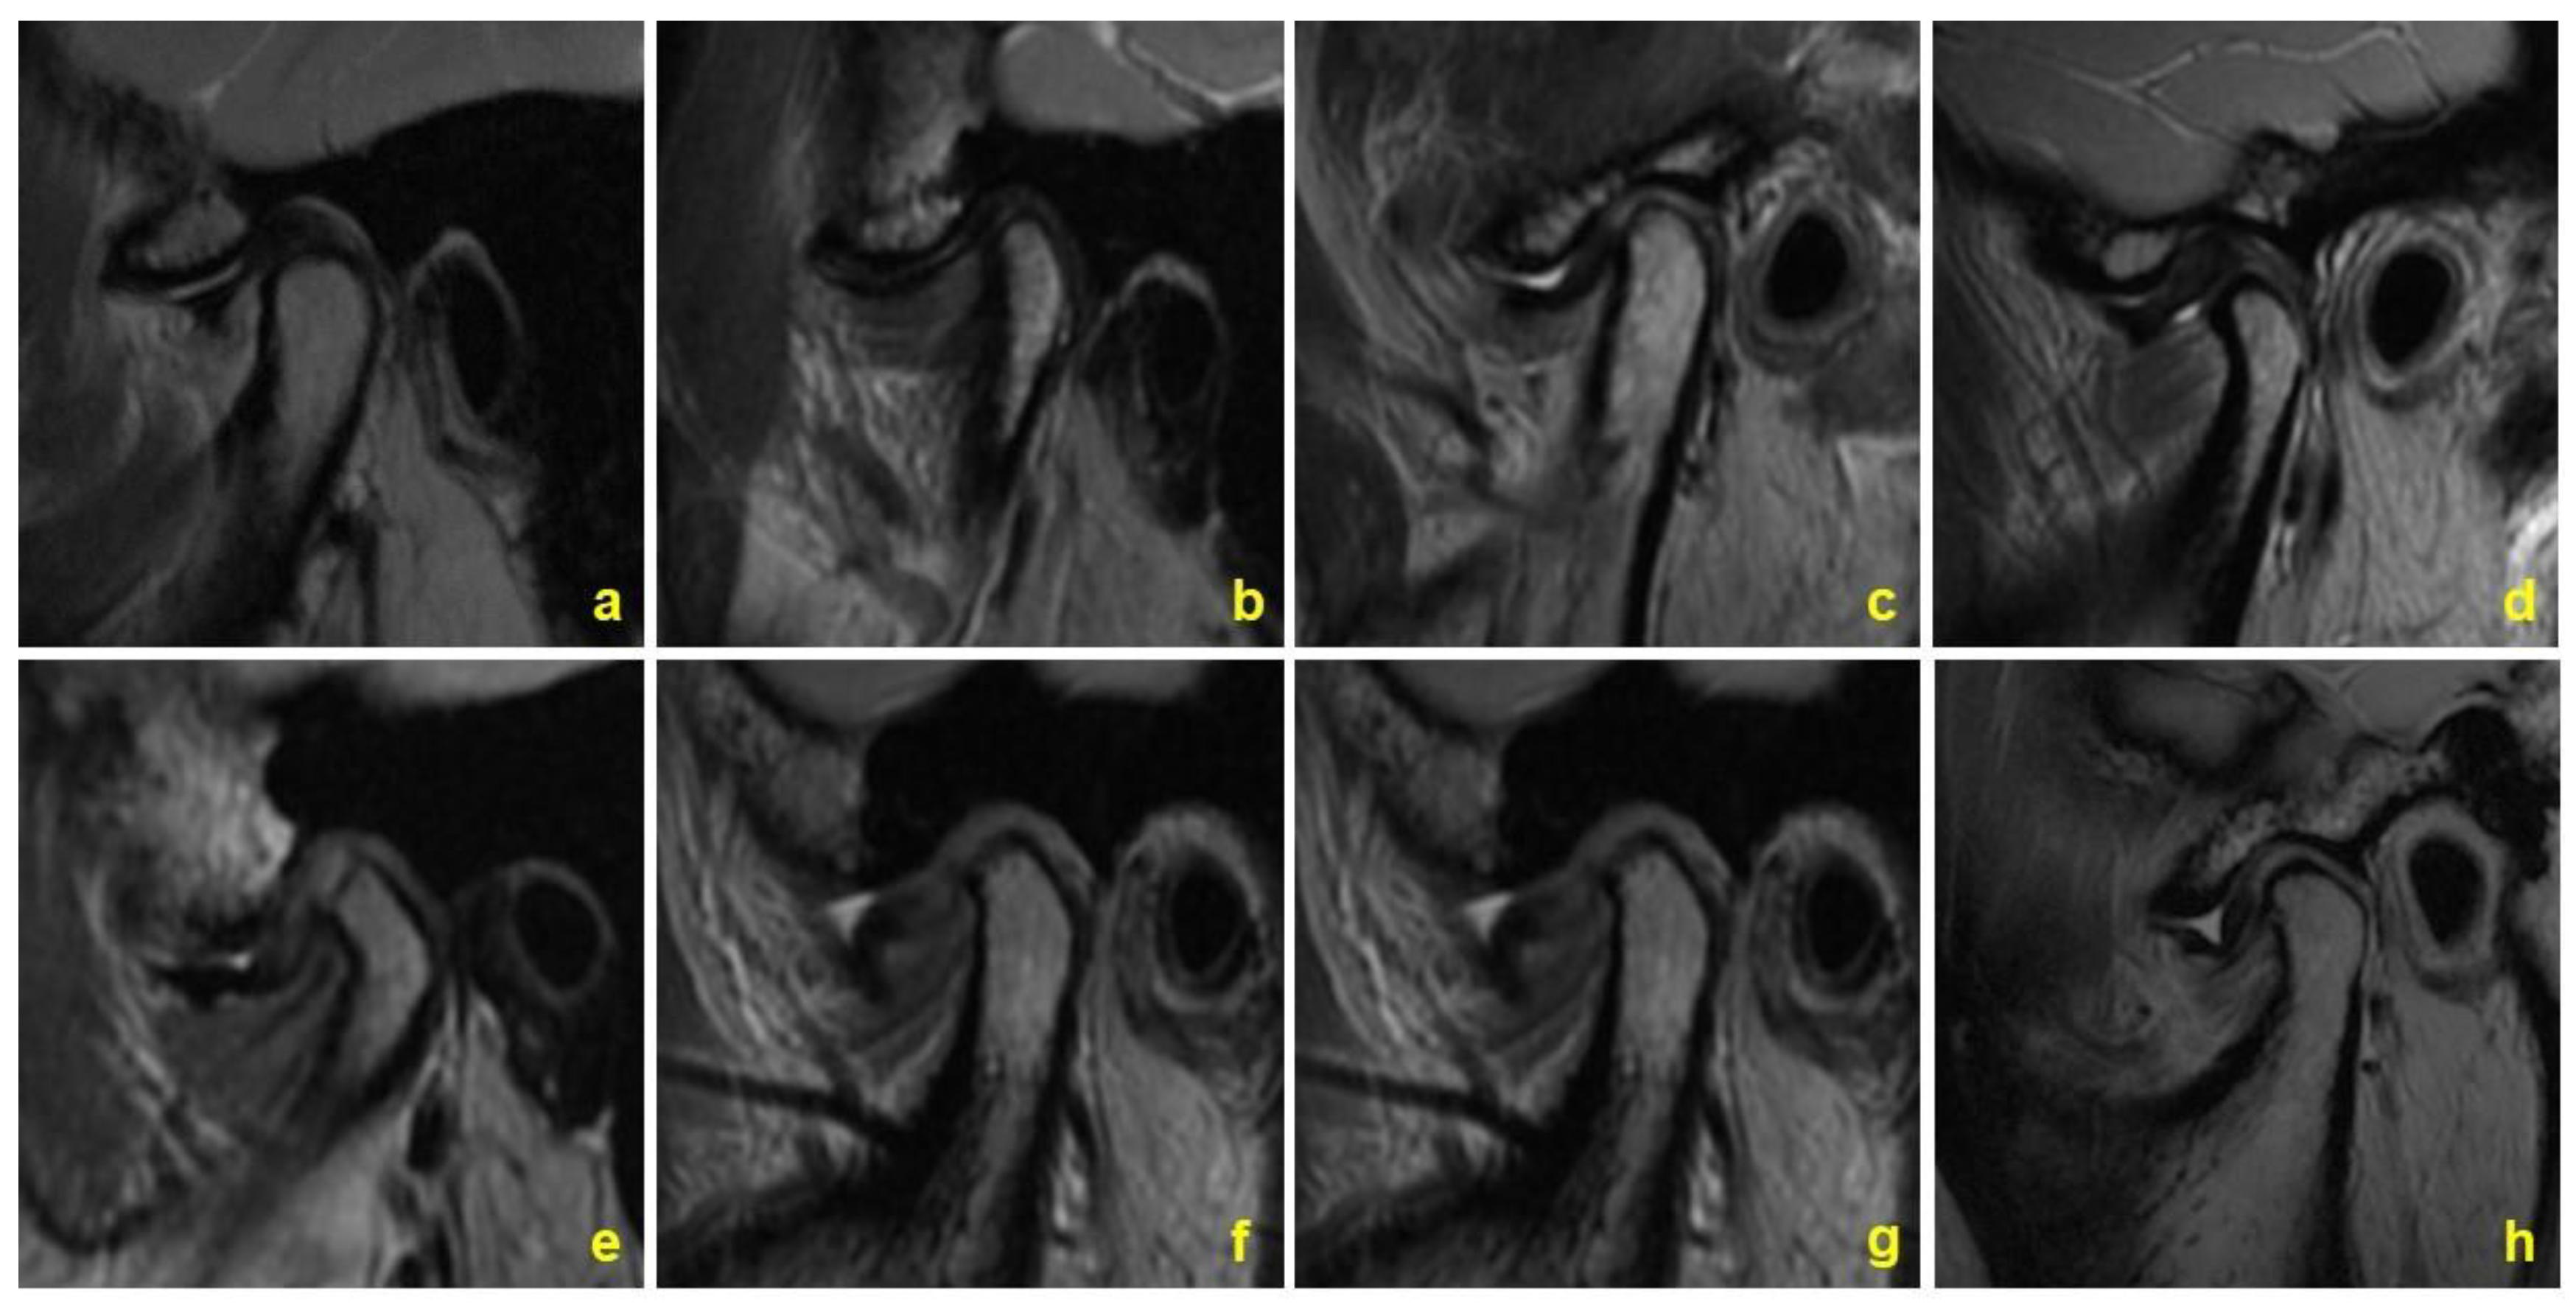

2.3.3. Classification of Disc Morphology

2.4. Statistical Analysis

- Zhang, Q.; Xiong, X.; Gong, Y.; Liu, F.; Liu, Y. Introducing a novice-friendly classification system for magnetic resonance imaging of the temporomandibular joint disc morphology. Oral Radiol. 2022. [Google Scholar] [CrossRef]